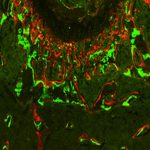

- IBEX uses antibodies so that HuBMAP researchers like Dr. Andrea Radtke at Germain lab can see cellular differences between healthy and tumor cells in lymph nodes. This is an image of follicular lymphoma lymph node showing stromal remodeling, a-SMA (orange) and SPARC (cyan), around B cell follicles (purple). a-SMA (orange) labels fibroblasts, CD20 (purple) labels B cells, SPARC (cyan) labels macrophages, stroma, matrix interactions.